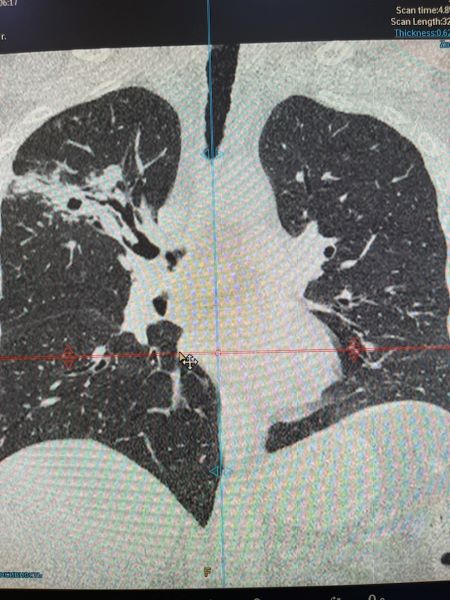

Врачом-рентгенологом, КТ-диагностом Якушевой И.А. пациенту было проведено исследование органов грудной клетки, нативным методом (без контрастирования), на МСКТ фирмы Филипс, после которого на многочисленных, тонкосрезовых томограммах, справа в верхней доле выявлена дополнительная тень в виде зоны консолидации с просветлением в центре, формирующейся полости, с отточной дорожкой к корню лёгких. Других видимых изменений не определялось.

По Cito ( в течении часа) были выполнены описание и расшифровка, с записью на цифровой носитель. По итогам исследования поставлено заключение: «Инфильтративный туберкулёз с распадом».